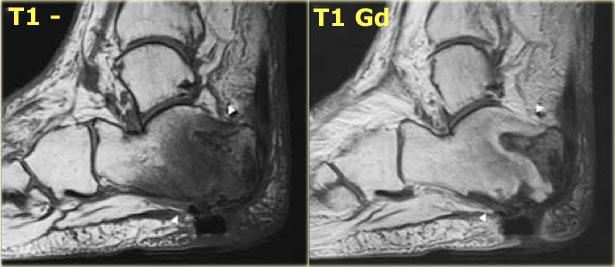

Dấu hiệu bóng ma

Dấu hiệu bóng ma gợi ý viêm xương khớp thần kinh có kèm theo viêm tủy xương.

“Dấu hiệu bóng ma” đề cập đến sự kém rõ nét của bờ xương trên hình ảnh T1 không tiêm thuốc, các bờ này trở nên rõ ràng sau khi tiêm thuốc tương phản.

Đây là hình ảnh của một bệnh nhân bị viêm xương khớp thần kinh có kèm theo viêm tủy xương.

Các vùng viêm tủy xương thể hiện rõ hơn trên hình ảnh T1 có tiêm thuốc tương phản so với hình ảnh T1 không tiêm thuốc.

Phù tủy xương, vốn có tín hiệu thấp trên hình ảnh T1 không tiêm thuốc, sẽ bắt thuốc và trở nên sáng tương đương với tủy xương bình thường.